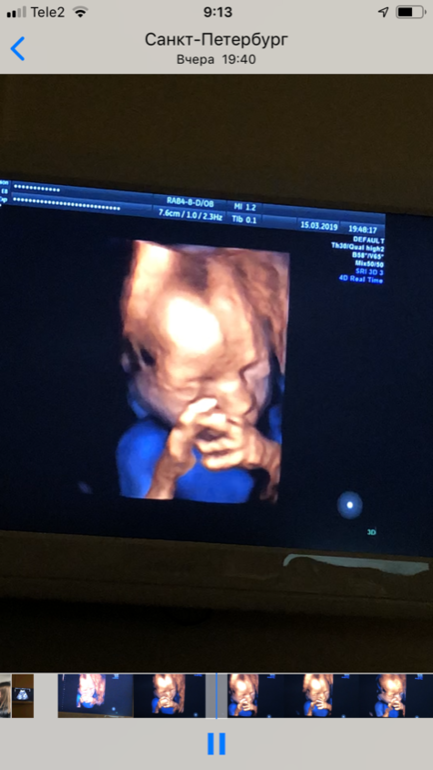

20 недель,2-ой скрининг,фото 3D

Результаты: УЗИ, КТГ, доплера, скринингаВчера было ровно 20 недель,2 скрининг,посмотрела как он вырос,такой хорошенький,палец сосал)) весит 350 гр. Все у него хорошо ттт. Хоть тут многие и говорили,что в 13 недель это рано для определения пола,но я считаю что нет,все зависит от врача,вчера специально даже спросила ее ошибалась ли она на сроке 13 недель с полом(первого,второго и этого третьего езжу только к ней скрининги делать), сказала,что с 13 недель она ни разу не ошибалась,что с такого срока уже все понятно. Вчера только подтвердила,что это ещё один мальчик😂. В спб она одна из лучших узи специалистов и кто скрининги делает идеально. Вдруг кому понадобится фамилия ее Лисина,работает в роддоме на фурштатской. Малыш вчера идеально лежал,шевелился во всю,показывая себя во всей красе и во всех ракурсах,видимо хотел угодить отцу,который тоже приехал посмотреть)) И фото мне на память,на ББ всегда проще зайти и посмотреть фото,чем потом искать их дома)) 😄😄